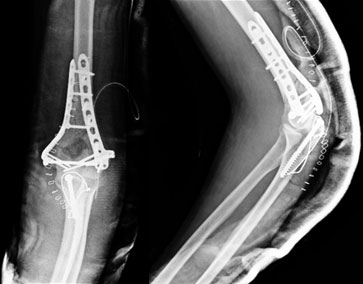

After surgery

In the surgery the fragments were brought back into place and a congruent joint surface was restored. The fracture was fixed using locked plate on both the columns. The Olecranon was osteotomized for getting a better view of the joint, which was later fixed with a tension band. |